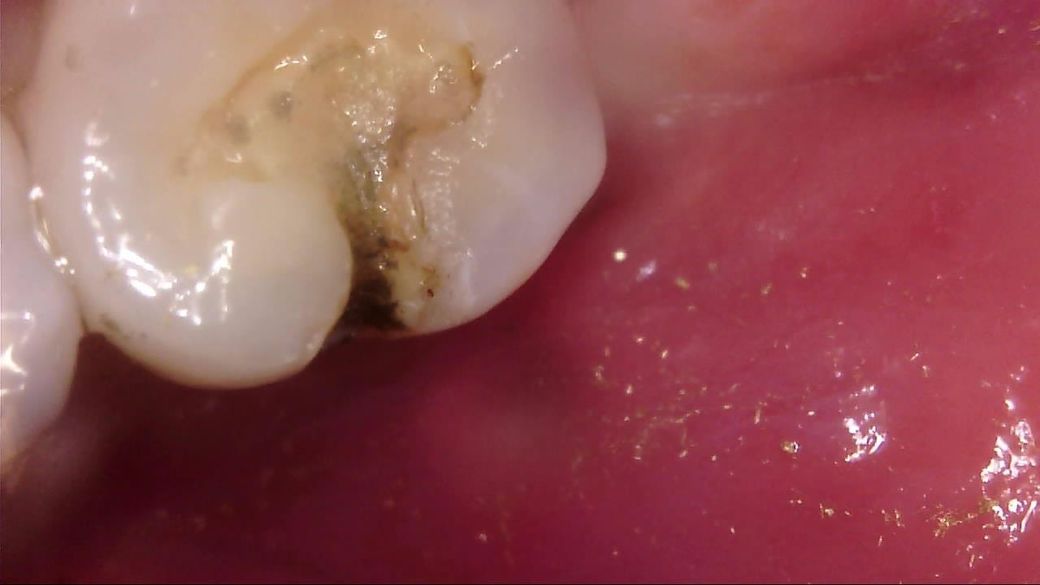

이차 우식이 상당히 깊게 발생하였는데, 치료 과정에서는 아래 사진과 같이 선생님께서 아래와 같이 일부 갈색 부분을 남긴 채 치아 삭제를 마치고 보철을 진행해 주셨습니다.

선생님께서는 "해당 부분은 착색 부위로, 이대로 덮어도 무방하다"라고 말씀 주셨고, 저 역시 더 이상 파고들어가면 신경치료가 예상되어 최선의 치료를 해 주셨다고 생각합니다.

• 2번 째 사진

사진에 보이는건 일단 착색과 2차 충치가 섞여 잇는거 같습니다. 충치를 제거하는 저스피드 기구로 제거를 해보기너 눌러 봐서 단단하면 충치가 아닙니다.

사진으로 보이는 부분은 충치에 어느정도 영향을 받은 부위는 맞습니다. 하지만 감염이 되어 있는것으로 보이지는 않습니다.

착색은 아니고 이환 상아질 남긴 것 같습니다 감염 상아질은 깔끔하게 다 제거 됐습니다